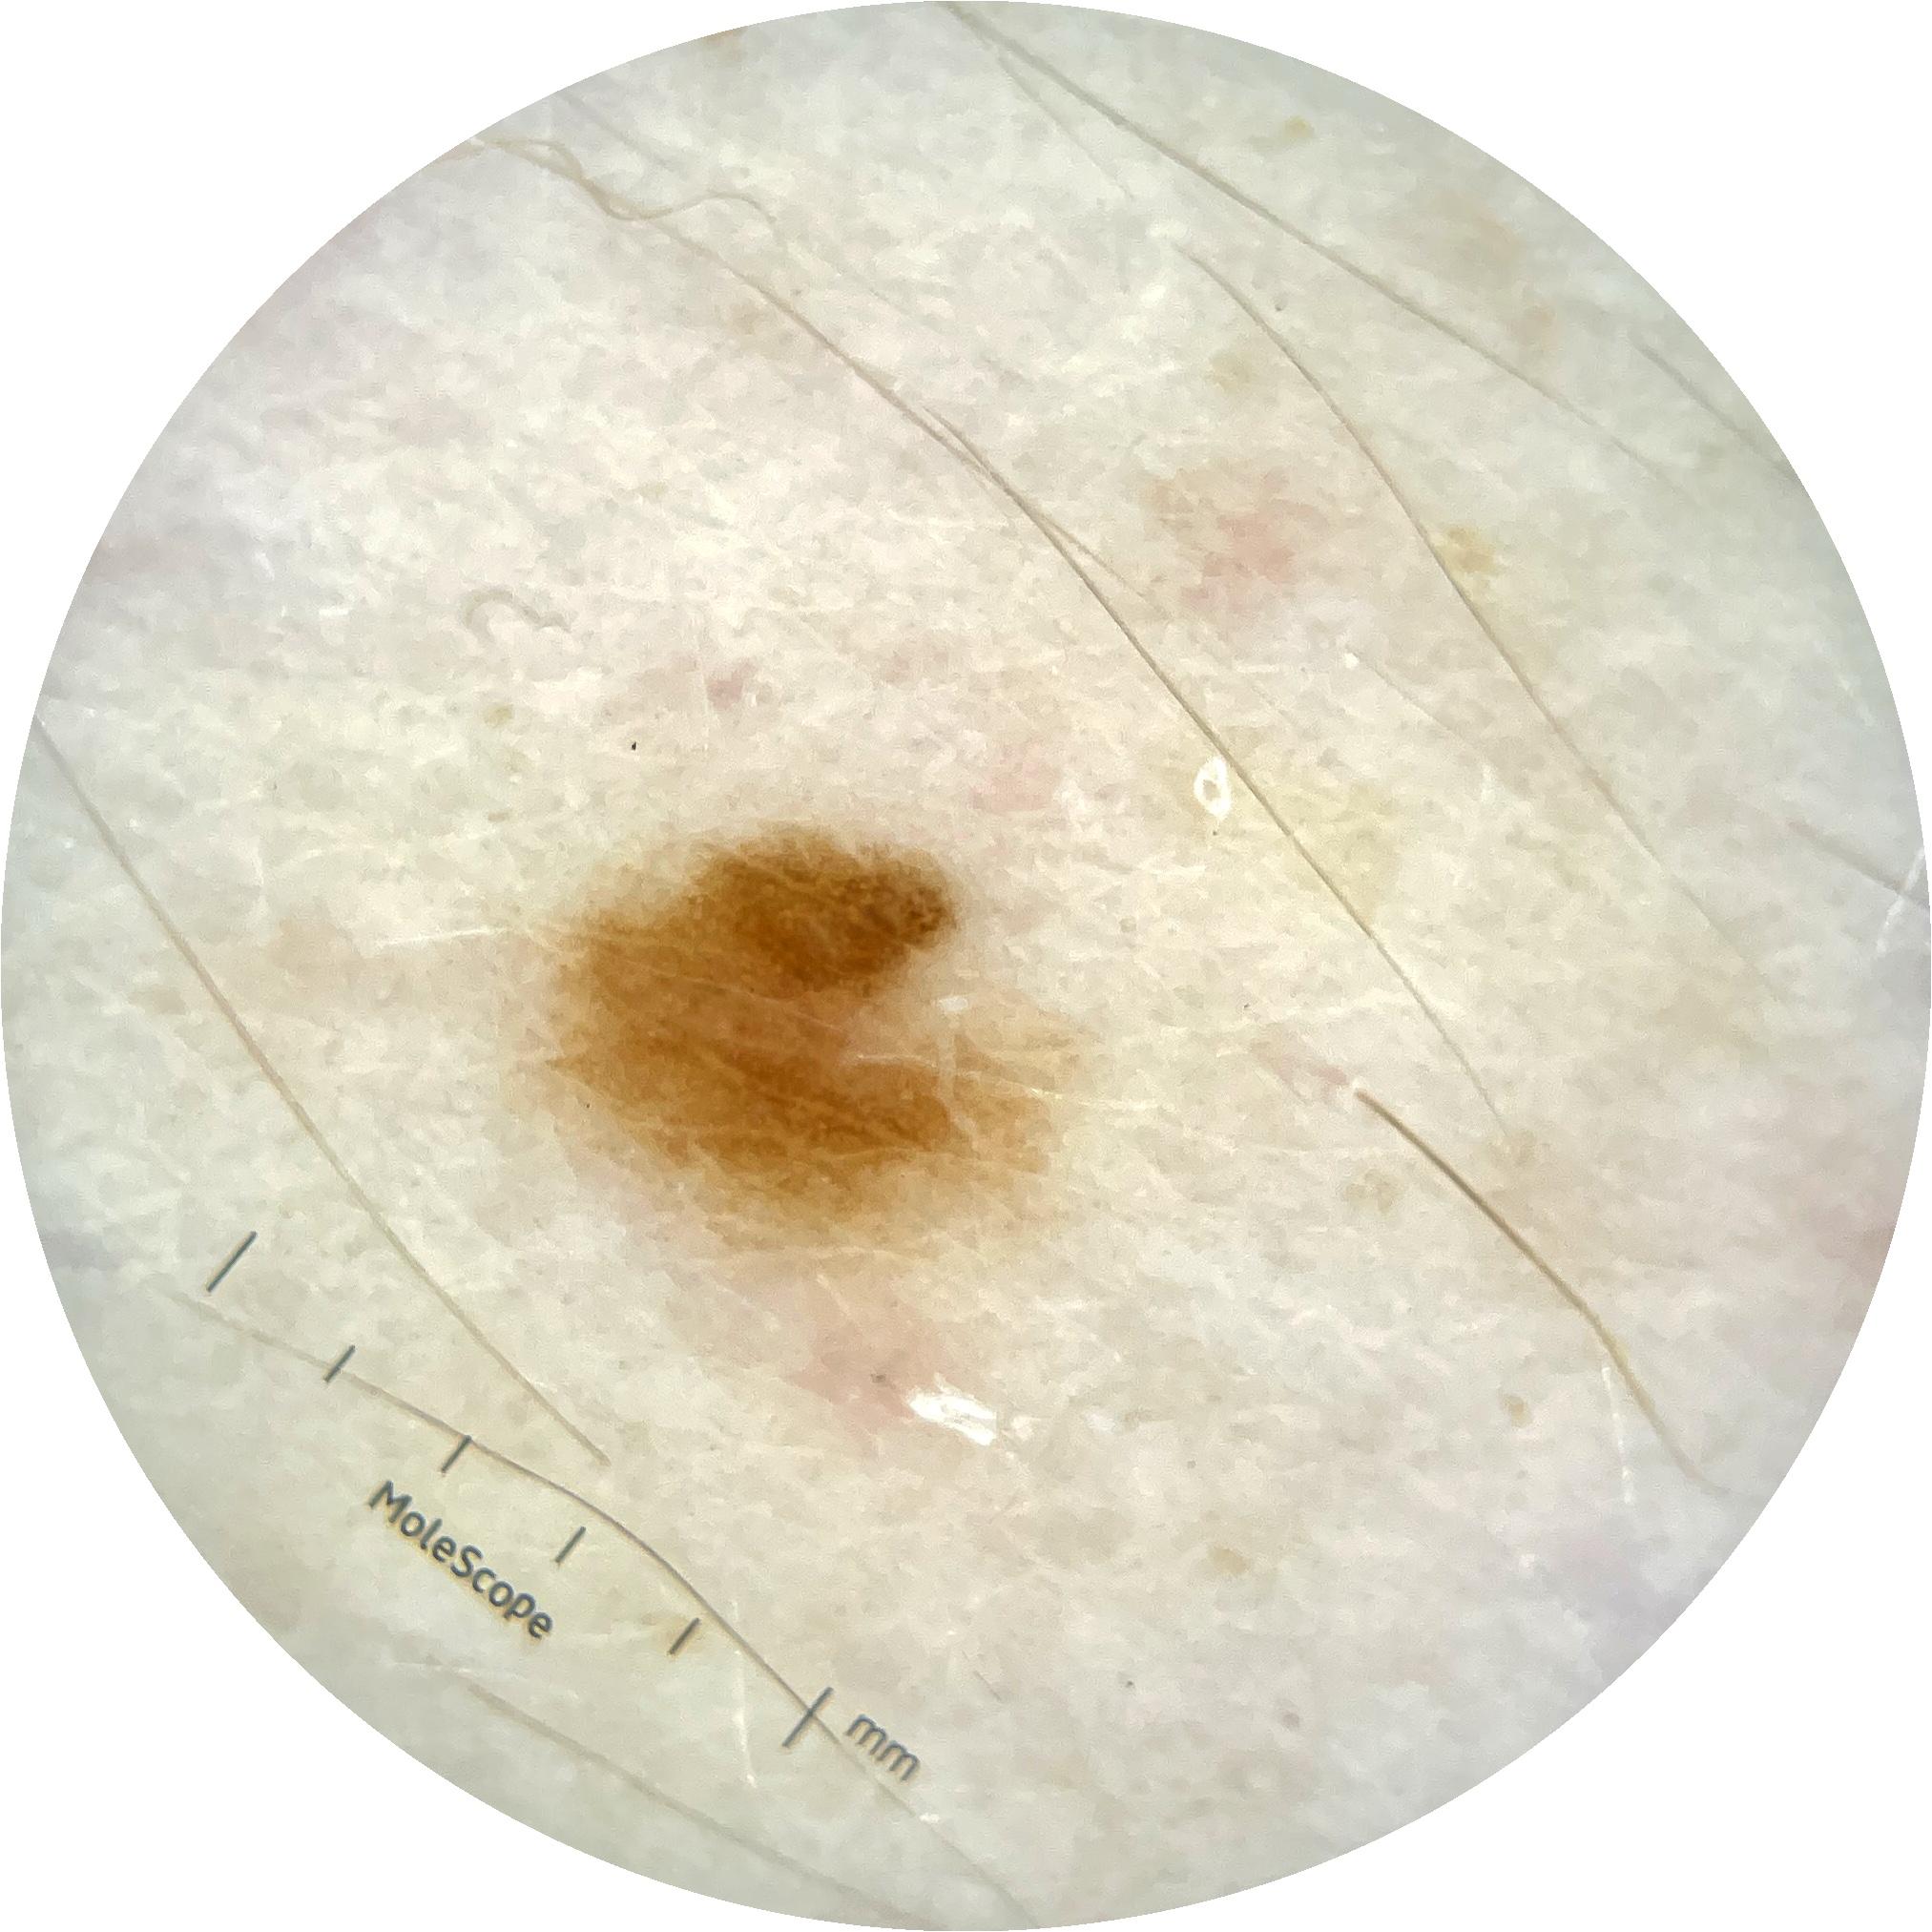

ISIC_9785574

Information

2003 x 2003

MEL-SELF Trial, https://www.sydney.edu.au/medicine-health/our-research/research-centres/melself-project.html

Field Value

acquisition_day 148

age_approx 45

anatom_site_1 Head and neck

anatom_site_general head/neck

concomitant_biopsy False

diagnosis_1 Benign

diagnosis_confirm_type single image expert consensus

family_hx_mm True

image_manipulation instrument only

image_type dermoscopic

lesion_id IL_0236417

patient_id IP_8456088

personal_hx_mm True

sex female